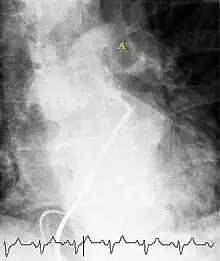

Fluoroscopic pulmonary angiography

Historically, the gold standard for diagnosis was pulmonary angiography by fluoroscopy, but this has fallen into disuse with the increased availability of non-invasive techniques that offer similar diagnostic accuracy.[68]

Pulmonary angiography has for decades remained the 'gold standard' for the diagnosis or exclusion of PE but is rarely performed now as less-invasive CT angiography offers similar diagnostic accuracy.